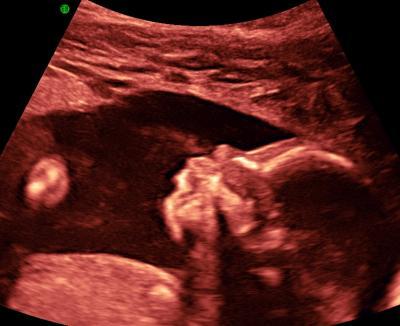

... MÄDCHEN Ihr glaubt es nicht, aber die Ärztin hatte den Schallkopf gerade aufgelegt, da fragte sie uns: "Möchten Sie das Geschlecht wissen?" Sie hat sich in voller Pracht präsentiert *lach* - war anscheinend unerwartet, denn hinterher waren die Beinchen wieder fest zusammengepresst... Jetzt müssen wir verschärft auf Mdchennamen-Suche gehen :D Insgesamt sind wir rundum zufrieden mit dem Organscreening: Alles ist TOP. Keinerlei Unauffälligkeiten. Allerdings bin ich von der Art der Untersuchung ziemlich entäuscht: Sie hat etwas mehr als 1/2 Stunde gedauert und ich habe kein einziges 3D-Bild. Die Maus lag ungünstig dafür, meinte die Ärztin. Ich war davon ausgegangen, dass die Unteruschung fast ausschließlich in 3D stattfindet... Wie dem auch sei - ist jetzt gelaufen und die Hauptsache ist, dass alles in Ordnung ist. Haben am 28.06. noch mal einen Termin gemacht, in der Hoffnung, dann mal 3D zu sehen. Liebe und glückliche Grüße, Brita

Schööööön ein Mädchen, freu mich auch das es bei mir wohl wieder ein Mädel wird. Das Bild ist voll süß, sieht aus als würde sie gerade ein Liedchen pfeifen. Welche Richtung an Namen gefällt dir denn? Grüße Jenny